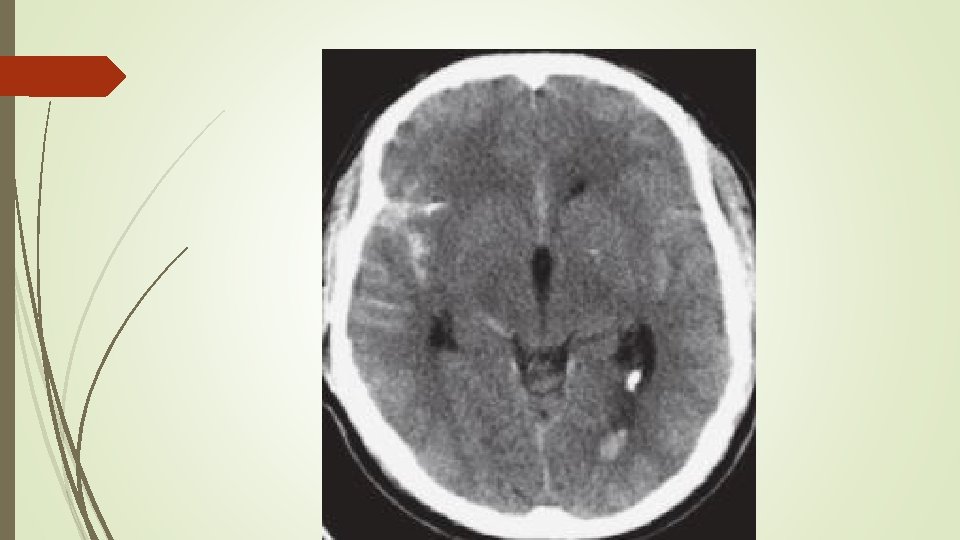

Özel kafa yaralanmalari Serebral kontüzyon ve intraserebral kanama § Sıklıkla SAK ile ilişklidir. § Künt travma ile aynı tarafta yada karşı tarafında olmakta. § Hemen yaralanma sonrası BT normal olabilir. Subaraknoid kanama § Parankim ve subaraknoid damarların yırtılması ile oluşur § Orta-ciddi TBY li hastalarda en sık anormal Bt bulgusudur. § SAK ı olan hastalarda mortalite 3 kat artmıştır

Özel kafa yaralanmalari Epidural hematom; § Kafa tası ve dura mater arasında kan toplandığında meydana gelir § Orta meningeal arter yırtılmasıyla meydana gelir. § Klasik öykü lucid periyodunu takiben bilinç kaybı ve hızlı nörolojik ölümdür. Ancak bu tablo vakaların az kısmında meydana gelir. § Arter kanaması olduğu için saatler içinde herniasyona neden olabilir.

Özel kafa yaralanmalari Subdural hematom; § Köprü venlerin yırtılmasıyla meydana gelir. § Dura mater ile araknoid arasında hematom oluşumuna neden olur § Aşırı atrofik beyinler, yaşlılar ve alkolikler akut subdural hematoma daha yatkındır. § Akut (ilk 2 hafta) ve kronik (14. günden sonra) olabilir. § Akut subdural hematom BT de sütür hattını geçen hiperdens görünürken, kronik subdural hipodens görülür.